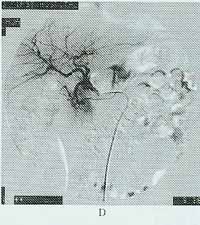

2、血管造影:疑有急性腸系膜缺血的患者,平片排除了其他急腹症,無論腹部體徵如何,均應早期作血管造影,這樣不僅能鑑別大血管閉塞是由血栓形成還是栓子栓塞引起,還能診斷出非閉塞性缺血,血管的狹窄程度和範圍。栓子傾向於栓塞在腸系膜上動脈主幹起始處的遠側或其分支內。栓塞近側有造影劑充盈,而其遠側血管不顯影。血栓形成通常在該動脈起始部3cm內,表現為血管突然中斷,可伴有反應性血管收縮,管徑普遍變小。因有側支循環形成,故梗阻遠端可有不同程度的充盈;非閉塞性腸系膜缺血腸系膜上動脈及其分支有各種不同的表現:瀰漫性狹窄,腸系膜上動脈多數分支起始部局限性狹窄,腸系膜上動脈分支狹窄和擴張交替,動脈弓痙攣,壁內血管充盈不足等。

急性腸系膜上動脈梗死對高度懷疑腸系膜動脈缺血的病人,排除其他急腹症後,無論外科是否決定行剖腹探查術,均應儘早做選擇性腸系膜動脈造影,一旦診斷明確,首先予腸系膜動脈復甦,積極改善腸系膜灌注不足和緊急外科手術治療。及時套用各種血管擴張劑,如罌粟鹼、組胺、酚苄明、胰高糖素、多巴胺、前列腺素E等。其中套用最多的是罌粟鹼。經導管立即開始罌粟鹼灌注,以30~60mg/h,加入生理鹽水中滴注,以擴張腸系膜血管,改善血流,可避免腸切除或減少切除範圍。根據血管痙攣緩解的情況決定罌粟鹼是否停藥或維持。如有血管擴張,則繼續輸入藥物,並連續拍片,待狹窄血管恢復正常後停用。通常1天已足,但也可持續4~5天。但有肝功能不全的病人使用罌粟鹼可導致低血壓,因此低血壓患者禁用。在腸缺血可逆期,手術摘除血栓可能治癒;而當腸壞死階段,則需同時行栓子摘除及腸切除術。動脈內注射妥拉唑啉25mg,可使阻塞的血管或末梢血管顯影。各型急性腸系膜缺血均伴血管痙攣,它可在導致缺血的因素已獲得糾正後仍持續存在。鏈激酶和尿激酶是纖溶酶原活性物質,能使血栓中的纖維蛋白分解,但全身套用有大出血的危險。因此臨床套用受到限制,局部套用利多弊少,可用小劑量鏈激酶(1萬~2萬U)在發病48h內經血管造影導管注入,儘量與血栓直接接觸,可達到溶栓目的。但應注意,溶栓治療不是手術治療的替代方法,只有在病人不能耐受手術時採用。